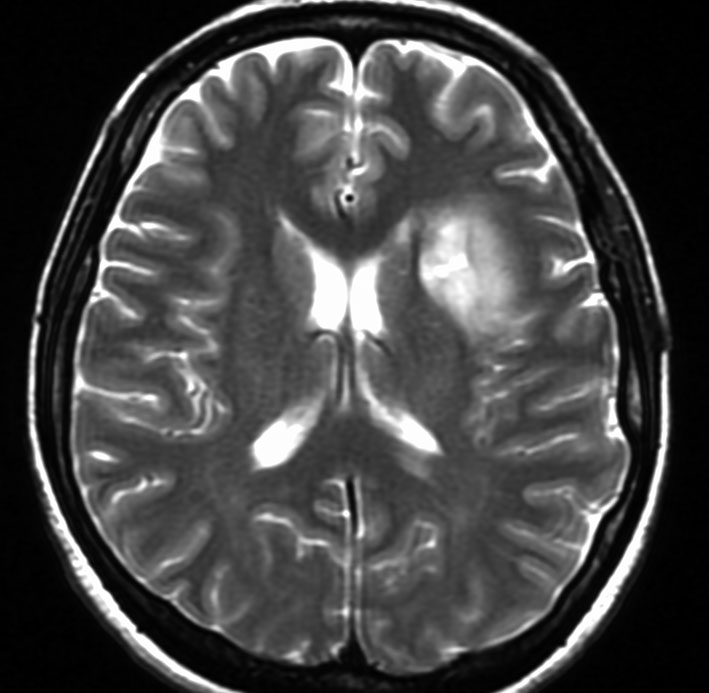

定位放射線治療前

典型的な脳転移のMRIです。腫瘍は,リング状にガドリニウム増強され,内部が腫瘍壊死になっています。腫瘍周囲の脳浮腫がとても強いのが転移の特徴的画像所見(右側のT2強調画像)です。この転移巣に対して,35グレイ・5分割の定位放射線治療が加えられました。